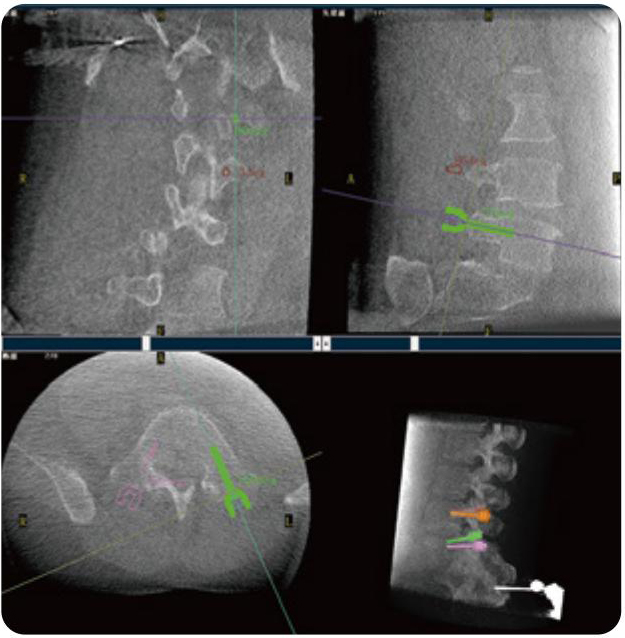

PL300B可應(yīng)用于多節(jié)段脊柱外科手術(shù),輔助醫(yī)生定位病灶部位,為脊柱外科手術(shù)(經(jīng)皮椎體成形術(shù)、椎弓根螺釘內(nèi)固定術(shù)等術(shù)式)提供術(shù)前手術(shù)流程規(guī)劃、入釘位置、角度可視化引導(dǎo),模擬仿真入釘輔助。

PL300B搭配普愛醫(yī)療自主研發(fā)生產(chǎn)的平板3D C形臂,借助一體化自適應(yīng)配準( 軌跡配準)技術(shù),通過追蹤C形臂三維采集軌跡,自動完成圖像坐標建立和系統(tǒng)坐標配準。配準精度更高,操作步驟少,系統(tǒng)運作效率高。